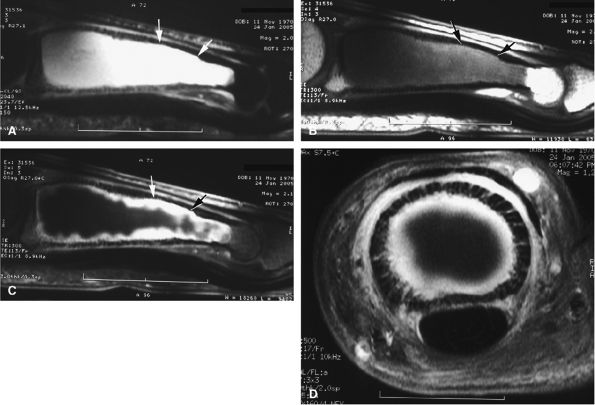

FIGURE 11.47 ● Jersey finger. (A) Sagittal T2-weighted image. (B) Coronal post-contrast T1-weighted images. (C) Axial T1-weighted image. Distal avulsion of the FDP tendon is shown with the proximal end (white arrows) at the metacarpophalangeal joint (type I). The tendon is wavy in the palm (arrowheads). The empty digital canal (in C) may mimic a remnant tendon, but the FDS tendon (asterisk) is alone in the canal.